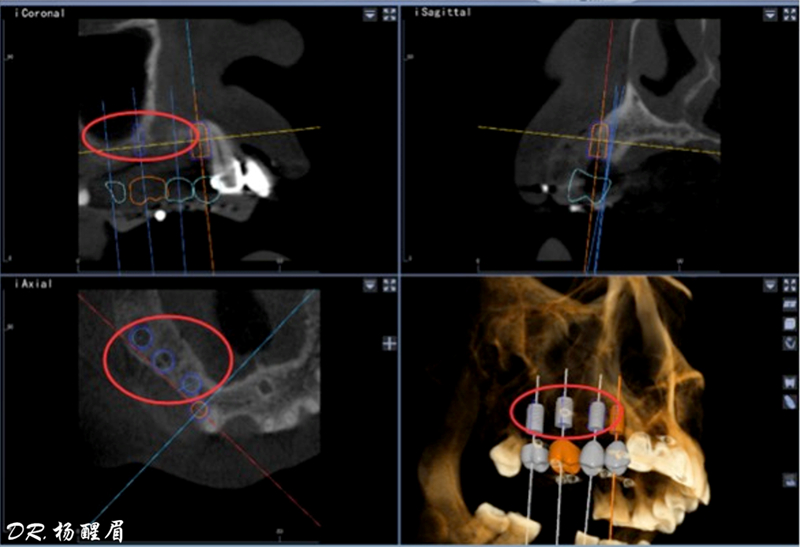

®根據(jù)CBCT中牙冠顯影位置,按照修復引導種植的原則進行方案設計

®使用迪凱爾易植美導航軟件進行方案設計,確定種植體使用方案,以及種植位點,方向和深度

®多顆植體種植方案應盡量保持軸向在同水平線上

®按照術前方案進行備洞及植體植入,醫(yī)生可以通過屏幕軟件引導對手術中植入點、角度、深度實時追蹤

®對植體深度及方向進行確認